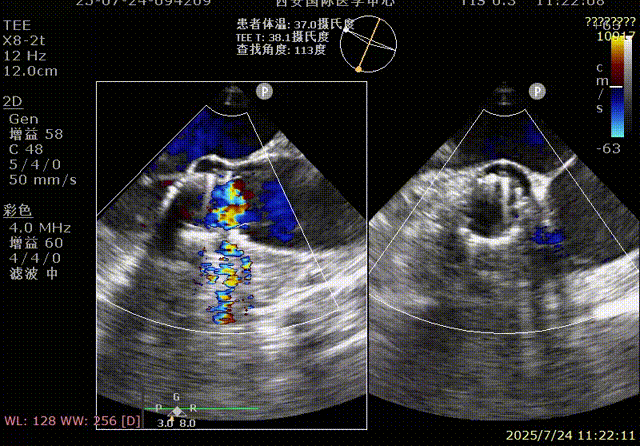

术前超声

术后超声